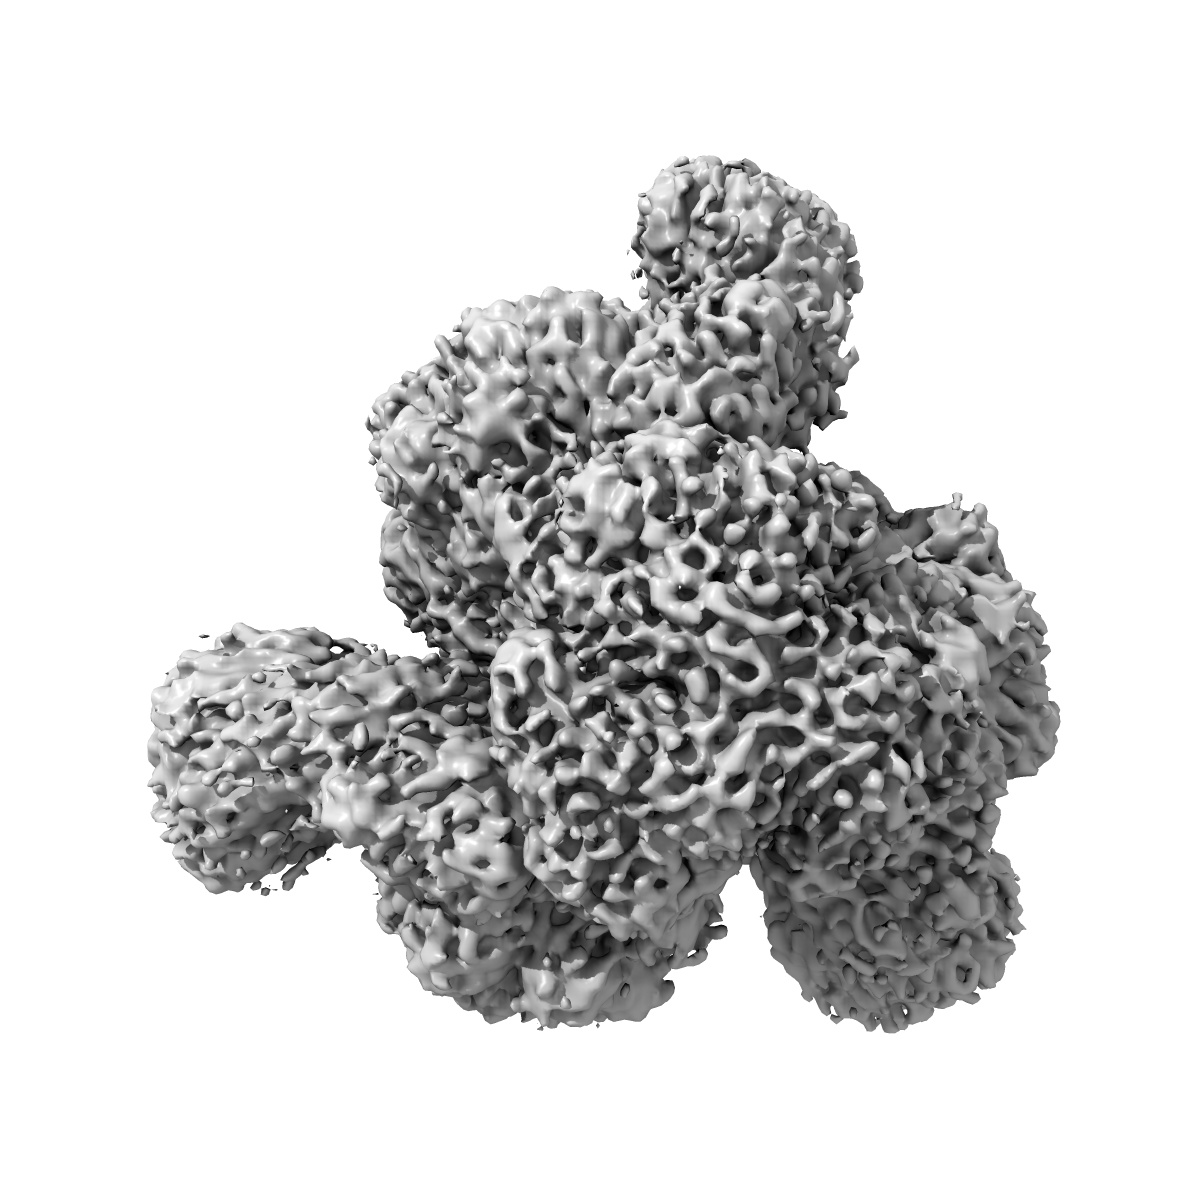

Cryo-EM structure of broadly neutralizing V2-apex-targeting antibody J033 in complex with HIV-1 Env

Single-particle4.2 Å

Sample: A complex of HIV-1 Env with antibodies 3BNC117 and J033